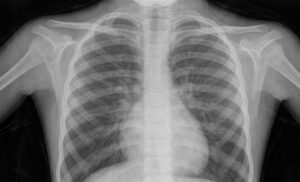

And then there’s man-made radiation like medical X-rays which have helped us see inside things for over a hundred years! So you can see that radiation is just part of our universe, and can be very helpful. Some radiation is good for you, and some is bad. Radiation has to be managed very carefully because if you do get too much, there’s a very real danger that you will feel very poorly.

X-rays are a wonderful addition to the world of medicine – they let doctors peer inside a patient without surgery, which is much easier and safer than opening a patient up.

X-rays are very similar source of energy to a light. However, light is absorbed by your skin and mostly stops. A bit like when you throw a water balloon at a wall. But X-rays pass through the human body and out the other side. Imagine that water balloon passing all the way through the wall and out the other side.